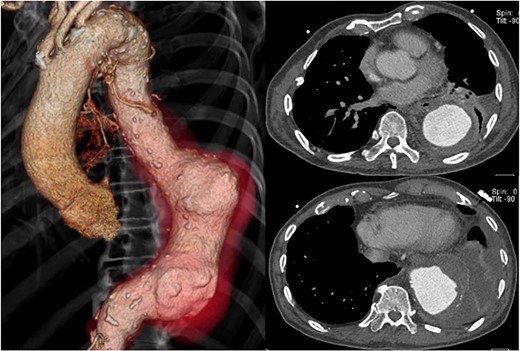

The patient had no back pain when he came to our hospital. His laboratory data on admission indicated severe infection, i.e. a white blood cell count of 15 080 cells/μL and C-reactive protein of 24.9 mg/dL. CT angiography showed an aneurysm, measuring 50 × 57 mm, with an effusion around it (Fig. 1). Because a mycotic aortic aneurysm was strongly suspected, intravenous antibiotic therapy was started with tazobactam/piperacillin hydrate, despite negative blood cultures.

CT shows a descending aortic aneurysm (a), 50 mm in diameter (b), surrounded by an effusion (c).